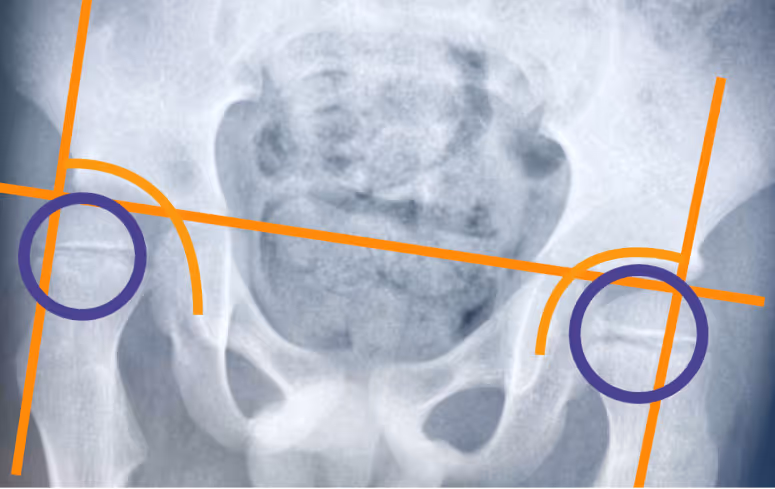

Диагноз ставит врач на плановом осмотре. Не все изменения в тазобедренных суставах можно увидеть на УЗИ, поэтому пациентам со СМА рекомендуется делать рентгенографию — по снимку врач определяет состояние суставов и решает, какие меры принимать.

Небольшое смещение головки бедренной кости, подвывих, полный вывих — все эти изменения ещё называют дисплазией тазобедренного сустава.

выраженный сколиоз, который вызывает стойкий наклон таза, тоже может привести к вывиху бедра [2].

Нестабильность тазобедренных суставов может привести к вывиху бедра. В такой ситуации нога примет вынужденное положение, может болеть — а это значит, что ребёнку будет сложно стоять, сидеть, и в целом качество жизни ухудшится.